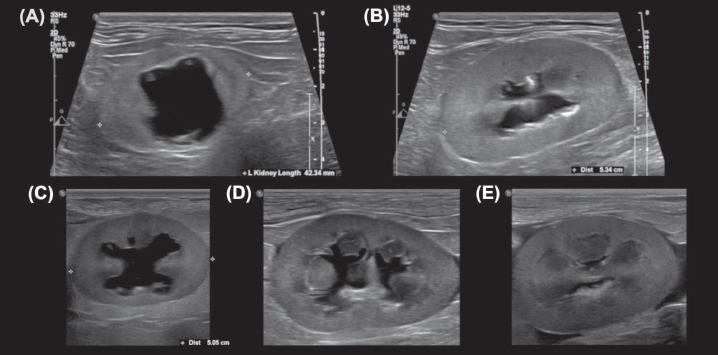

Supplementary 4. Examples of the ‟Dorsal crest-to-ureter” (DCU) (A) and ‟Dorsal pelvic width (DPW)” (B) measurements performed by observers.